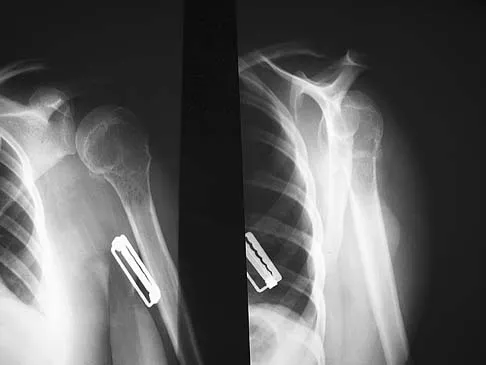

Question 15 High Yield

Figure 36a shows the current radiograph of a 65-year-old woman who slipped and fell. History reveals that prior to the fall she was actively functioning without pain. Figure 36b shows a radiograph obtained 1 year ago. Based on the fracture pattern, the failure is most likely related to

Detailed Explanation

The radiograph shows a fracture distal to the prosthesis in a stable, apparently well-fixed prosthetic stem. The well-fixed prosthesis-bone composite is stiff, creating a modulus mismatch between the proximal and distal femur. Therefore, the risk of fracture, particularly in osteoporotic bone, is increased at this level. Revision of the stem to a longer construct is unnecessary, and standard plate and screw fixation has been shown to yield union rates of greater than 90%. Nonsurgical treatment of fractures distal to the tip of the prosthesis results in high nonunion rates, reported to be from 25% to 42%. Johansson JE, McBroom R, Barrington TW, Hunter GA: Fracture of the ipsilateral femur in patients with total hip replacement. J Bone Joint Surg Am 1981;63:1435-1442. Bethea JS III, DeAndrade JR, Fleming LL, Lindenbaum SD, Welch RB: Proximal femoral fractures following total hip arthroplasty. Clin Orthop 1982;170:95-106.